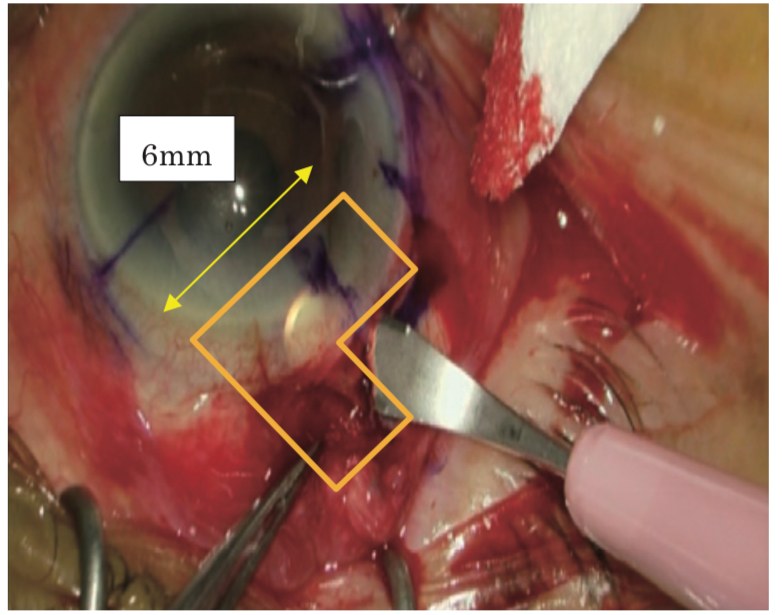

眼内レンズ偏位の患者さまは、20年ほど前に眼内レンズ縫着術というレンズの支えを眼の壁に縫い付ける手術を受けていましたが、2つあるレンズの支えのうち、片方の支えの縫合が取れてしまいました。10日くらい前から『見え方が不安定でいい時はいいけれど、ぼやけてしまう』という症状が現れましたが、もう片方の糸はしっかり残ってくれていて、レンズは眼の奥に落ちず留まってくれていましたので、その点は手術がしやすくてよかったです。しかし、この方のレンズは、ボシュロム製のP366UVという縫着専用のレンズが使われていましたが、このレンズはPMMAという硬いプラスティックでできていて、光が通る光学部の直径は6.5mmと大きめで、今、主に使われている眼内レンズはアクリルかシリコンの柔らかいレンズで切ることができるので、2.5mmくらいの切開創から取り出していますが、PMMAのレンズは切ることができないので、6mmほどの切開を作って取り出す必要があり、ちょっとだけ厄介でした。6mmの切開といっても、表面を切開するのは3mmほどで、残りの3mmは強膜(眼の壁)の中にトンネルを作り、トンネルの中で更に3mm眼の中に切開を入れ、トータルで6mmの切開創を作る“L字切開”という方法でレンズを取り出しました。単純に6mm切開するよりはキズの閉じもよく、切開による乱視も少なくよい方法だと思います。無事、レンズを取り出し、新しいレンズもきれいに入れることができてよかったです。